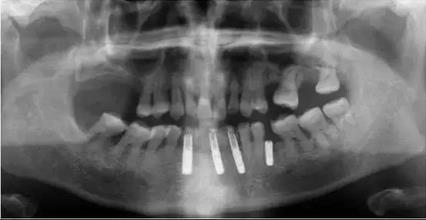

修復(fù)后全景片